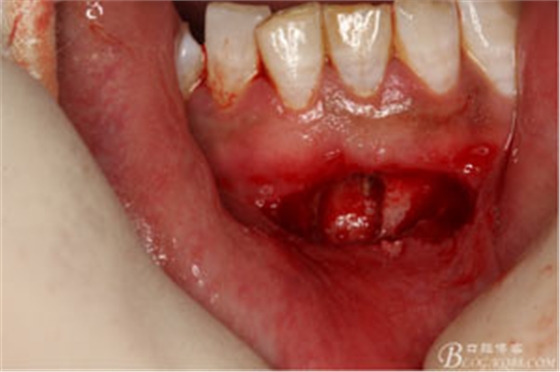

圖11.根尖切除后,并搔刮干凈后的31缺損的骨腔情況